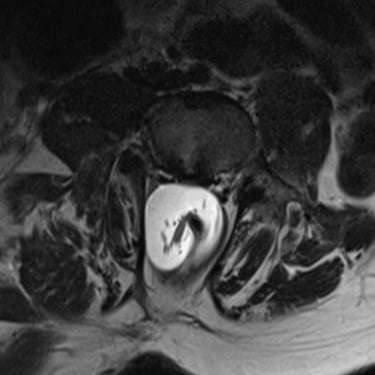

La médula anclada es una condición en la que la médula espinal queda fijada o traccionada anormalmente dentro del canal vertebral, generando síntomas como dolor lumbar, debilidad en las piernas, alteraciones sensitivas y disfunción urinaria. El tratamiento indicado es la liberación quirúrgica, un procedimiento microquirúrgico que busca desprender las adherencias y liberar la médula, permitiendo su movilidad normal. Se realiza con neuronavegación y monitoreo neurofisiológico para proteger las estructuras nerviosas. Esta cirugía, cuando se realiza oportunamente, detiene la progresión del daño neurológico y mejora la función motora y sensitiva del paciente.